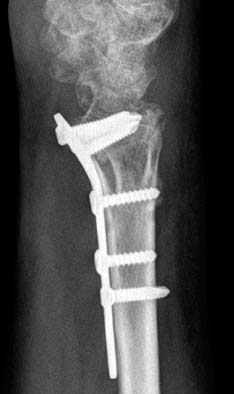

Fig. 7

The plate is fixed distally, and the flexor tendon can be ruptured by attrition.

jkfs-21-325-g007.jpg

Fig. 8

This juxtaarticular plate is fixed distal to the transverse ridge.

Fig. 7 The plate is fixed distally, and the flexor tendon can be ruptured by attrition.

Fig. 8 This juxtaarticular plate is fixed distal to the transverse ridge.